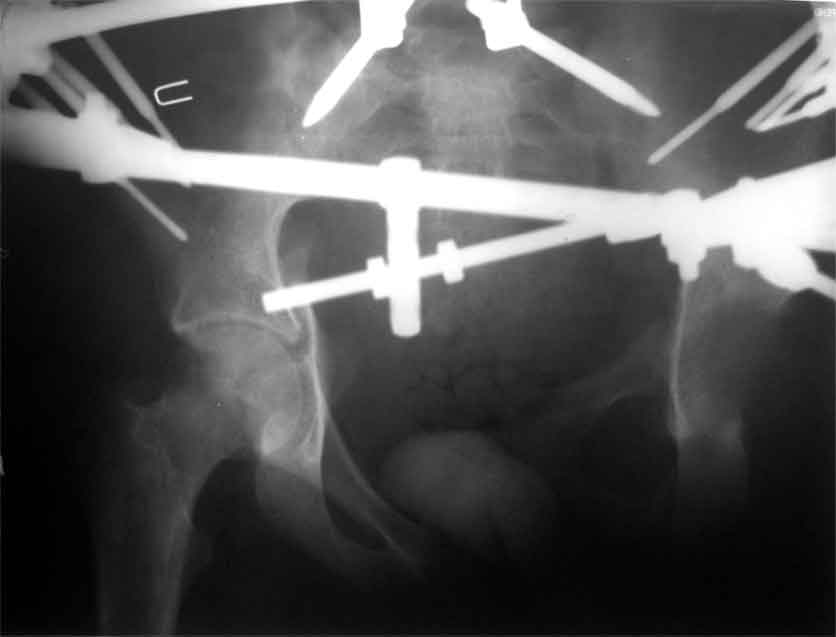

продолжение темы. не увидел энтузиазма в обсуждении. Вопросы прежние, первым этапом закрыто устранили вертикальное и передне-заднее смещение. Каким образом восстановить целостность тазового кольца, из каких доступов? Снимки в приложении

передне-неружным внебрюшинным доступом к лонно-седалищномц сочленению - синтез штангами(можно из заднего доступа, но хуже обзор и труднее репозиция), из этого же доступа к крыше вертлужной впадины - синтез реконструктивными пластинами(мы делали "ChM" тазовыми, хорошо себя зарекомендовали), передним доступом на лонное сочленение - синтез подобной пластиной. к задней колонне вертлужной впадины - задне-наружный доступ, синтез такой же пластиной. КРОВОПОТЕРЯ!!! возможно до 7л. мощная ангтибак. профилактика во время и после операции. до перехода на заднюю колонну оперировать в аппарате. бвл подобный случай, по снятии аппарата через 8 мес. - рецедив смещений сразу.